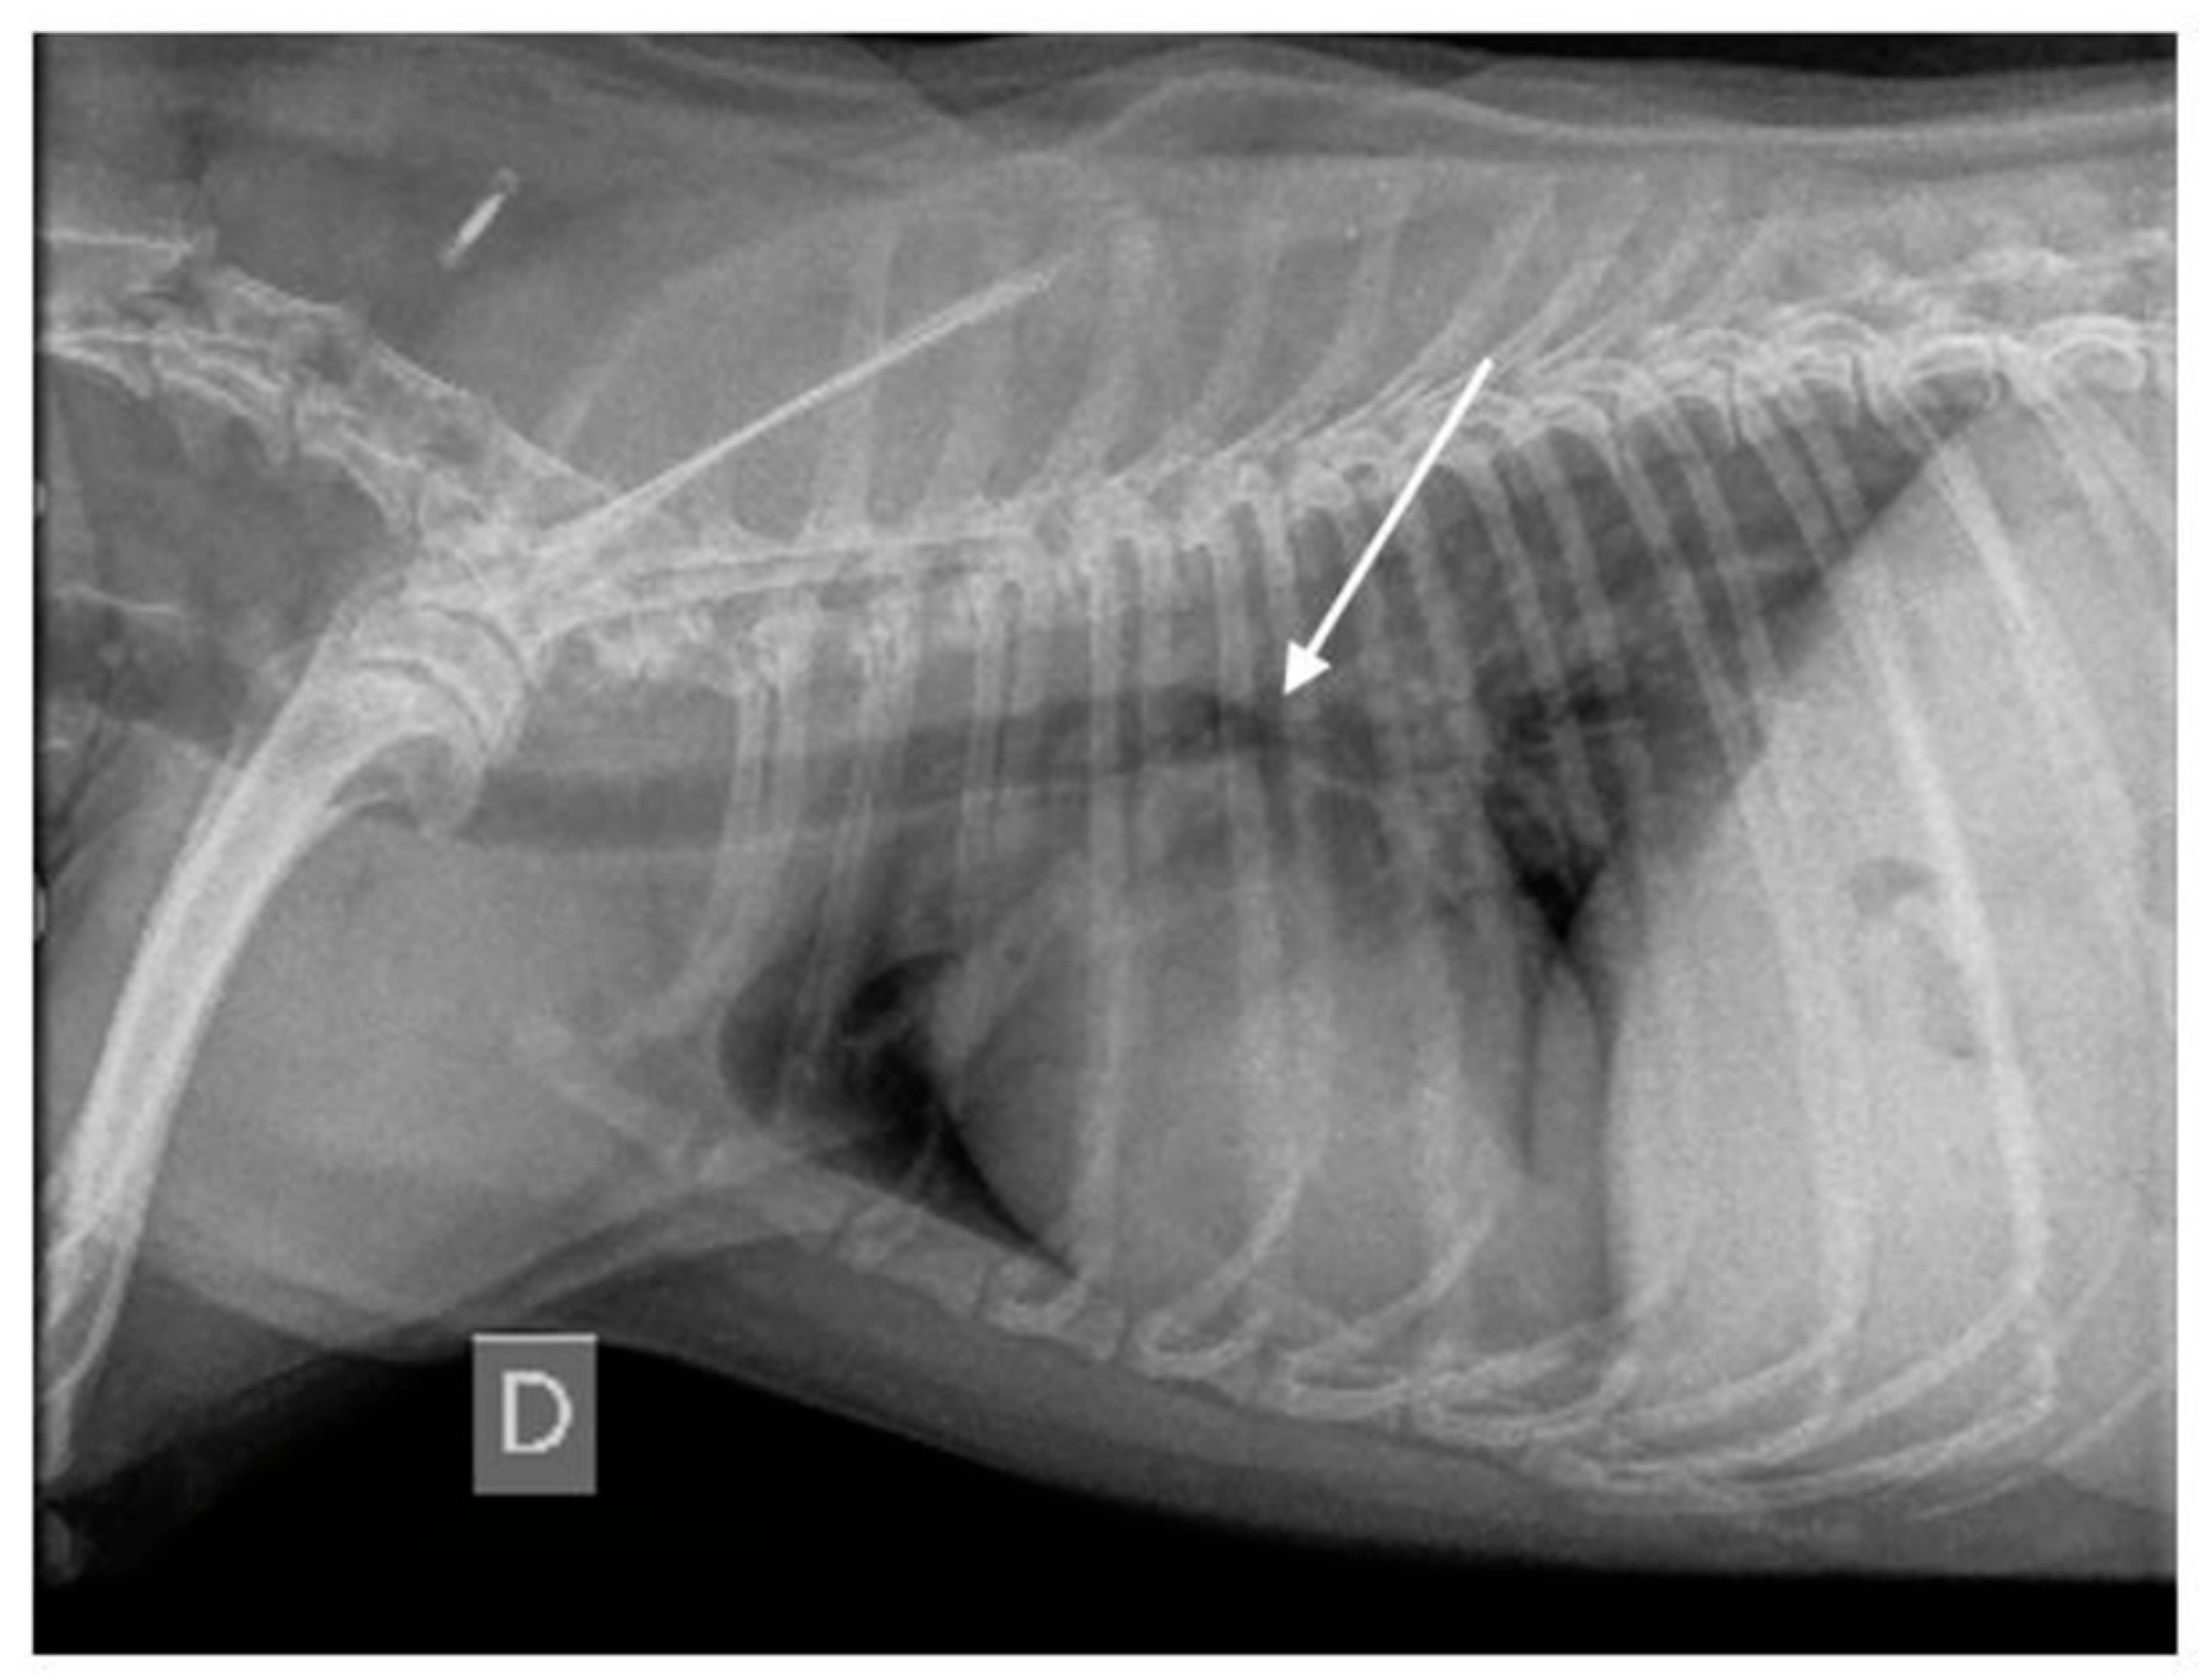

3.1.7. Thoracic Radiography Findings

3.2.1. Thoracic Radiography Versus Endoscopy